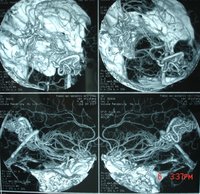

腦血管畸形1、腦動脈造影

腦動靜脈畸形有以下典型表現:①顯示畸形血管。這是特徵表現,呈一團管徑相仿相互糾纏的迂曲擴張血管。畸形血管團的範圍可小如指甲,大如手掌,多見大腦半球皮質.②異常粗大的供養動脈和引流靜脈伴局部循環加快。此為局部血流短路的表現。③血流分流現象:造影劑隨血流經畸形血管的短路大量流入靜脈,因此,血管畸形部分因血流量增加而顯影十分清楚。④血腫的表現:血管破裂出血致腦內血腫,血腫的主要表現為局部占位徵象,一股腦部動靜脈畸形無血腫時,腦血管不出現占位徵象,腦血管不移位。 2、CT表現:

5.腦血管造影:最可靠、最重要的診斷方法,動脈期可見血管團、供血動脈及早期顯現的引流靜脈。

4、腦血管造影是本病最可靠和主要的診斷方法,並能行血管內介入治療。

三術前準備

1、由於有多發的可能,術前應作全腦血管造影或雙側頸動脈造影,或按畸形血管部位推測,加作椎動脈造影。典型的腦動靜脈畸形包括供應動脈、畸形灶及引流靜脈三部分。通過造影應查清供應動脈來源及引流靜脈走向,畸形灶的部位及範圍,有無血腫等合併症,以及病人有無它處畸形。才能制訂出完善的手術計畫,也是手術成功的關鍵。